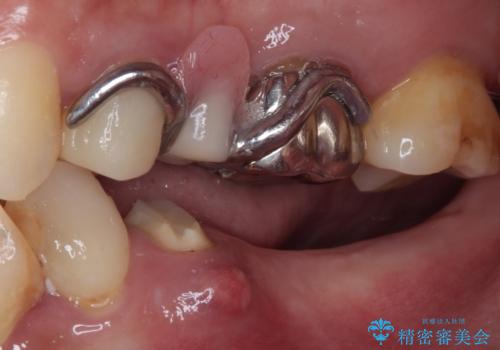

- むし歯を放置したままで、インプラント治療を希望して来院された患者様です。

左右ともにインプラントが必要な状態でした。

左下小臼歯は根管治療で対応する予定でしたが、診断のために歯肉を開いたところ頬側に垂直破折が認められたため、抜歯即時埋入インプラントによる補綴治療を選択することとしました。

右下は大臼歯部の歯は抜歯即時埋入インプラントにて、手前の歯は保存して補綴治療を行うこととしました。